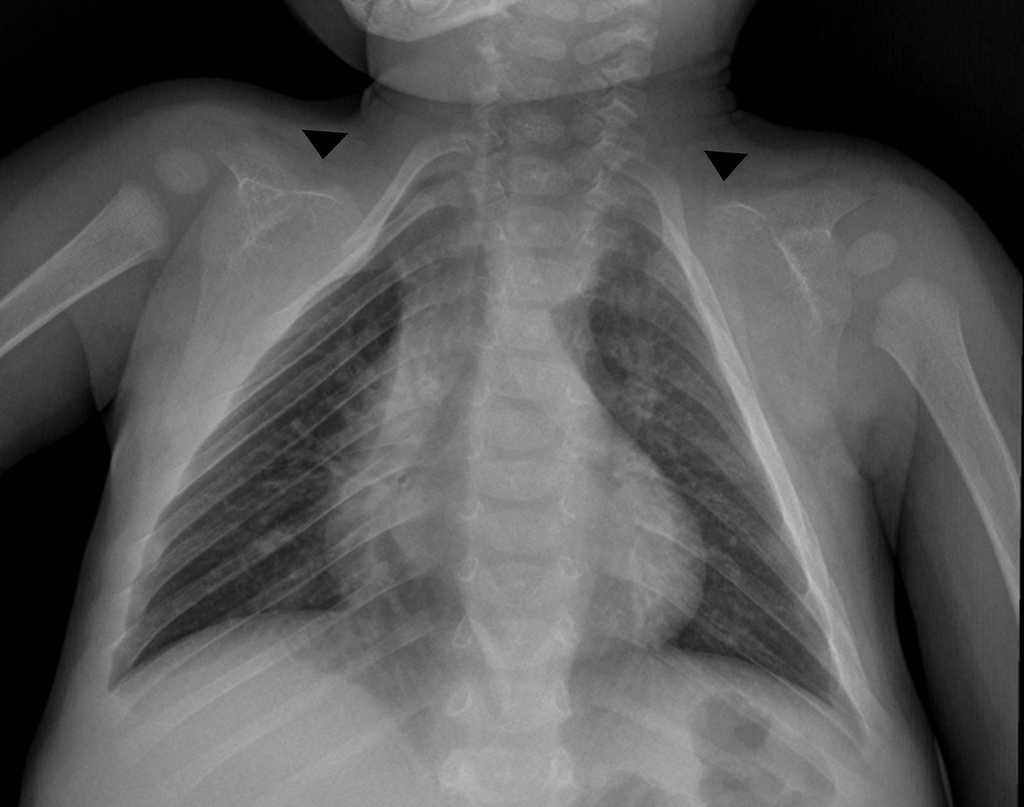

A pesar de su baja prevalencia, se considera necesario el conocimiento de esta entidad por parte del médico radiólogo para realizar un diagnóstico adecuado y oportuno. Por ello, comunicamos el caso de un niño de 3 años que consultó inicialmente por una caída desde aproximadamente 1 metro de altura, con trauma en miembro superior derecho. En la radiografía (Rx) se evidenció una fractura del cóndilo lateral humeral. No obstante, en el examen físico se encontró talla baja, hipertelorismo y alteraciones óseas craneales, consistentes en diastasis de suturas y persistencia de fontanela anterior abierta, además de macroglosia, paladar ojival, dismorfismo dentario (se sospechó diagnóstico de Síndrome de Pierre Marie Sainton en su forma esporádica), ausencia de clavículas y pectus excavatum. La Rx convencional de tórax anteroposterior demostró apariencia triangular del tórax y ausencia congénita de ambas clavículas (fig. 1), mientras que la Rx anteroposterior de pelvis reveló ausencia de osificación de las ramas iliopúbicas y osificación parcial del isquion, con ausencia de las ramas isquiopúbicas (fig. 2). No se ampliaron estudios para detectar anormalidades en el desarrollo óseo de manos y columna vertebral.

*Tórax

-Tórax en forma de cono

-Anormalidades claviculares (hipoplasia o aplasia de las clavículas, y clavículas discontinuas), siendo los tercios lateral y medio de la clavícula los más comúnmente afectados7

-Escápulas hipoplásicas